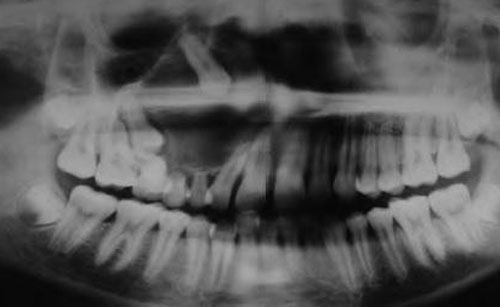

- рентген – на начальных этапах развития малоэффективный метод;

- компьютерная томография;